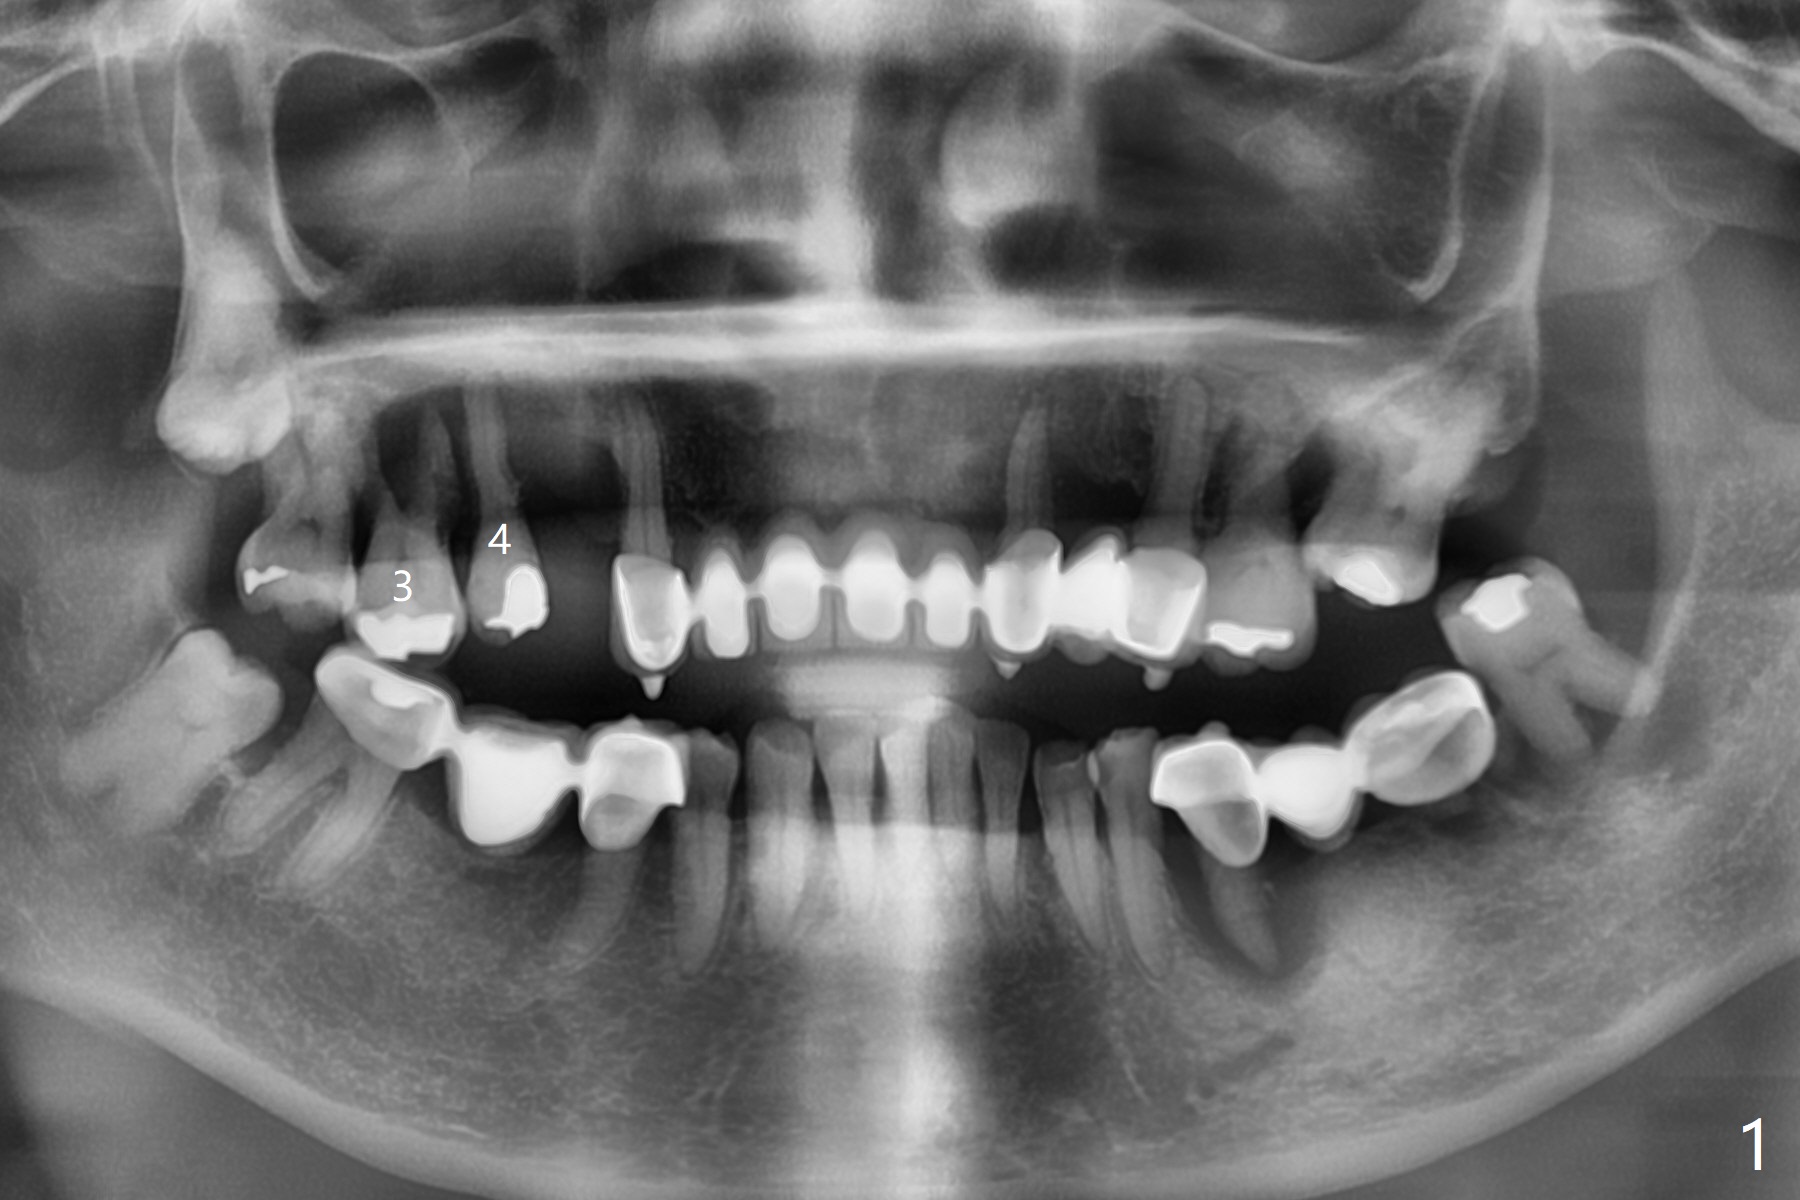

A 51-year-old woman has poor dentition with chronic periodontitis (Fig.1). She has financial constraint, but refuses RPD, insisting upon UR posterior implants first. After discussion of severe bone loss, she agrees with bone graft first (Fig.2-4). Since the bone atrophy is the most severe at #3 (Fig.5 coronal section; L: lingual), sinus lift (Fig.6 arrow) is conducted after extraction (black). Use sticky bone (Fig.7 red circles) and Titanium-reinforced Cytoplast (white) for socket preservation. Or if Magicore is able to achieve primary stability (Fig.8 green), an abutment (pink) will be placed for an immediate provisional (white). The latter are capable of holding bone graft in place. Since bone loss at #2 and 4 is less severe (Fig.9 sagittal section), their roots will act as walls to keep bone graft (Fig.11) in place after #3 extraction (Fig.10).